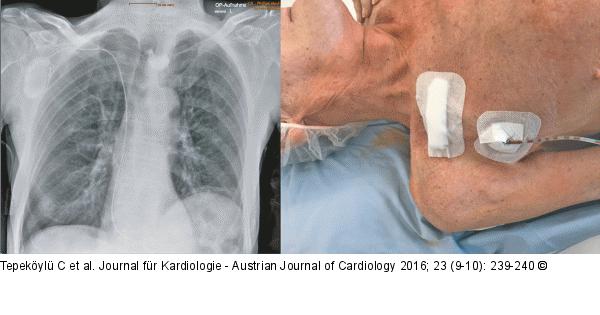

Abbildung 3: Herzchirurgie - Post-OP Thorax-Röntgen und postoperatives Ergebnis. In Lokalanästhesie wird ein VVIR-Schrittmacher implantiert. Die Implantation verläuft komplikationslos. Postoperativ zeigt der Schrittmacher eine regelrechte Funktion. |

Abbildung 3: Herzchirurgie - Post-OP

Thorax-Röntgen und postoperatives Ergebnis. In Lokalanästhesie wird ein VVIR-Schrittmacher implantiert. Die Implantation verläuft komplikationslos. Postoperativ zeigt der Schrittmacher eine regelrechte Funktion. |